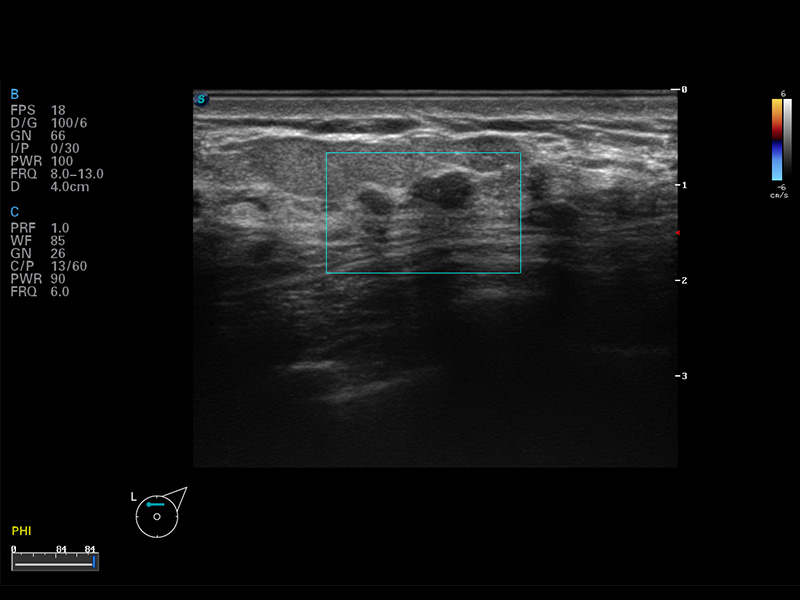

S8 EXP便携式彩色多普勒超声诊断仪是云顶集团官网研发的高端全身应用型便携彩超。高通道的VIS平台融合可视化(Visual)、智能化(Intelligent)和人性化(Smart)的特点,配以云顶集团官网自主研发生产的探头大家族,使您能够快速、准确的获得病人信息,提高工作效率的同时减轻疲劳。

μ-Scan微米成像

谐波成像

空间复合成像